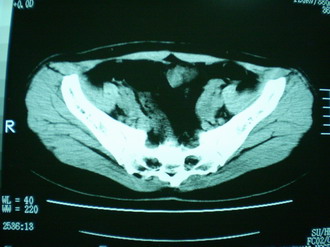

子宫增大,内可见类三角形低密度区,子宫后方可见类圆形团块状影,内部密度不均匀,可见靶样结构,结合病史考虑1子宫后方宫外孕(宫内假孕囊形成)2子宫肌瘤合并妊娠

子宫明显前倾,增大,宫颈增大呈分叶状。子宫直肠窝见不规则形水样低密度。(膀胱胀尿不理想)

考虑:1、宫颈部占位;

2、子宫直肠窝少量积液(盆腔炎所致)。

考虑肌瘤堵塞子宫颈管导致宫腔积液。

考虑:1、宫颈部占位(宫颈癌?);

2、子宫直肠窝少量积液。

1、前曲子宫,2、宫颈部占位?3、盆腔及右输卵管积液?宫内积血?4、左侧卵巢囊肿。